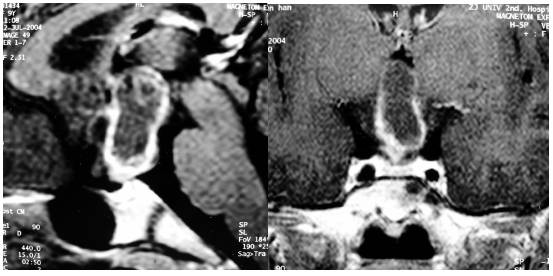

积极对症治疗,加强营养,谨慎地补液以维持电解质平衡,并予琥珀酸氢化考的松静脉滴注治疗,但肌强直及粗震颤无明显改善,仍有不规则高热,意识模糊。出院康复治疗。术后4月余随访症状稍有好转,但仍不能自理。术后1年随访,症状明显好转,可独立行走,生活自理(图4)。内分泌激素检查正常。复查MRI显示双侧尾状核和壳核软化灶(图5)。

图5.一年后复查MRI显示双侧尾状核和壳核软化灶